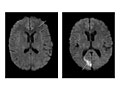

Magnetic resonance imaging (MRI) is a test that uses a magnetic field and pulses of radio wave energy to take pictures of the head. In many cases, MRI gives information that can't be seen on an X-ray, ultrasound, or computed tomography (CT) scan.

For an MRI of the head, you lie with your head inside a special machine (scanner) that has a strong magnet. The MRI can show tissue damage or disease, such as infection or inflammation, or a tumor, stroke, or seizure. Information from an MRI can be saved and stored on a computer for more study. Photographs or films of certain views can also be made.